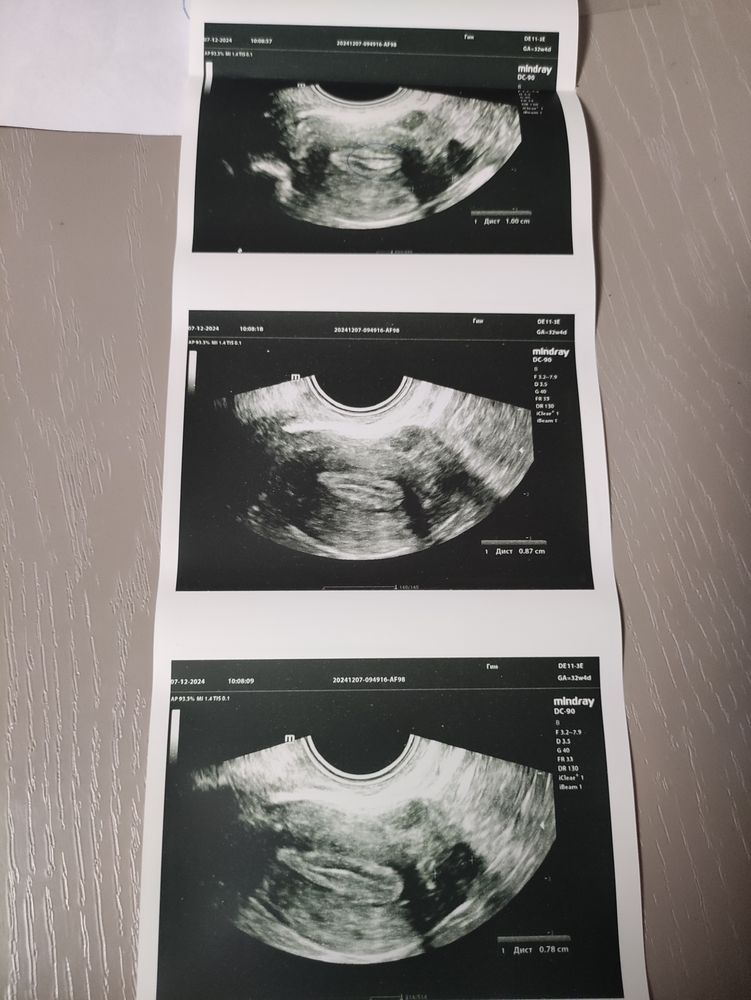

Тут прерывистая линия. Поэтому подумали на полип.

Если нет жалоб, то можно подождать . полипы до 1см самостоятельно могут оторваться и выйти с месячными… либо это не полип вовсе, а складка эндометрия.